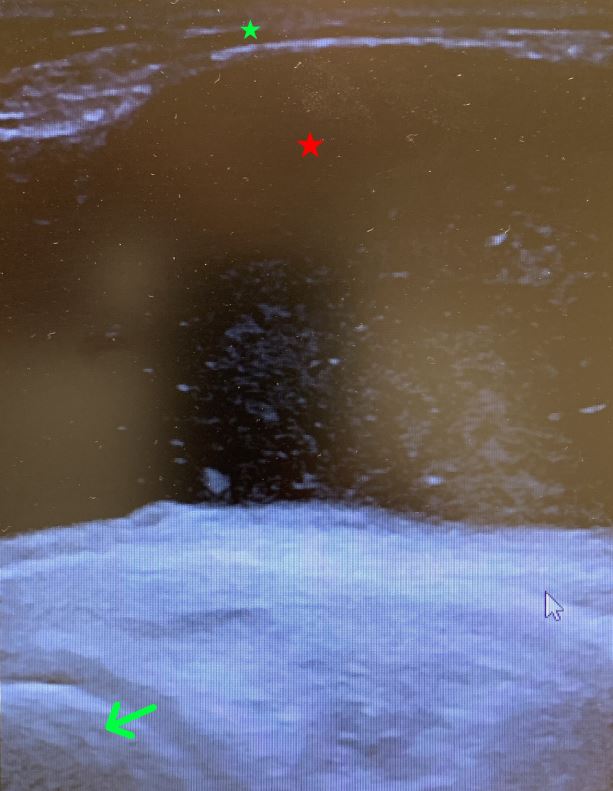

Eine 64 Jahre alte Patientin mit bekannter Gonarthrose litt seit Monaten unter einer zunehmenden Schwellung der linken Kniekehle. Immerhin konnte sie das Knie noch frei bewegen. Am medialen Gelenkspalt war ein lokaler Druckschmerz auslösbar. Ein Ultraschall führte zur Diagnose.

Schwellung in der linken Kniekehle (l.), Darstellung in der Sonografie (o.): Zyste (rotes Sternchen) zwischen Subkutis (grünes Sternchen) und Knochen, u. a. der dorsalen medialen Femurkondyle (grüner Pfeil).